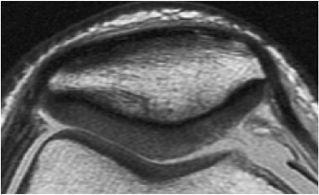

FIGURE 7.6 ● (A) Sagittal fat-suppressed T1-weighted gradient-echo MR image sequence of the knee demonstrates a focal high-grade partial-thickness cartilage defect overlying the medial femoral condyle (arrowheads). In the equivalent time required to acquire this single pulse sequence, cartilage-sensitive fast spin-echo MR sequences in two planes—sagittal (B) and coronal (C)—can be obtained, in which the depth of the lesion is much better delineated. (Reprinted by permission of SAGE Publications, Inc., from Am J Sports Med, in press.)